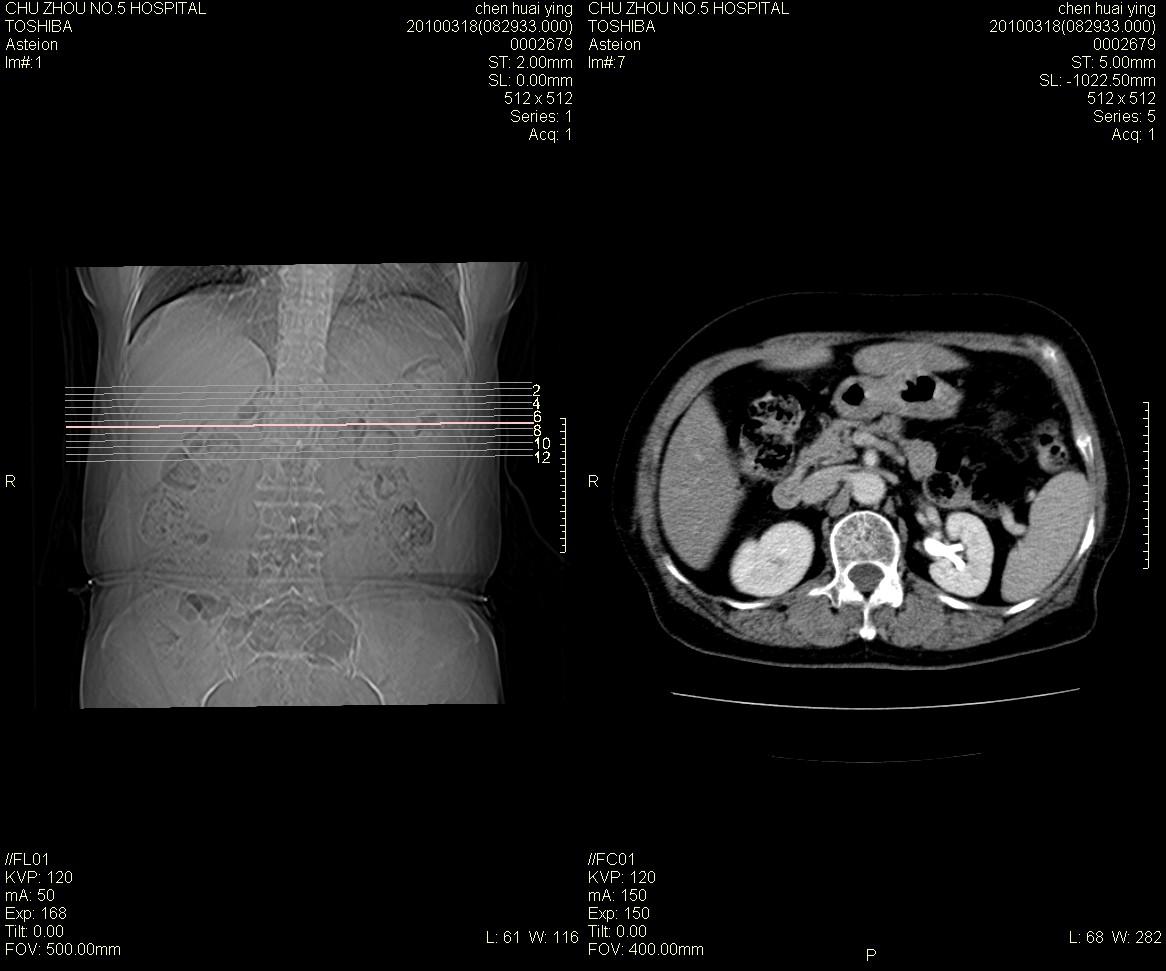

标题: CT25148 肾上腺增强

ct25148增强图片

动脉期太早了,扫的有点低。考虑良性占位右侧肾上腺嗜铬细胞瘤并坏死囊变可能性大,神经鞘瘤不排除。

右侧肾上腺占位性病变,病人是否有高血压?嗜铬细胞瘤?

右侧肾上腺嗜铬细胞瘤并坏死囊变可能性大